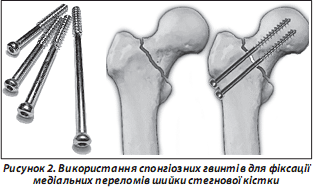

Численними дослідженнями доведені позитивні якості компресуючих спонгіозних гвинтів (рис. 2).

Досягти позитивних результатів оперативного втручання допомагає використання сучасної рентгенослідкуючої апаратури та ретельне дотримання вимог одномоментної репозиції за рекомендованих методик [4, 13, 15]. Гвинти повинні бути відповідної довжини та вводитись у вигляді рівностороннього трикутника при перетинанні ШСК. Нижній гвинт обов’язково (особливо при остеопорозі) слід проводити дотично до дуги Адамса. Різьбовий кінець гвинта не повинен наближатися до субхондральної замикальної пластинки головки стегнової кістки менше ніж на 6–10 мм. Другий і третій шурупи проводяться проксимальніше, паралельно першому та дозволяють запобігти виникненню дорзальної дислокації і ротації головки. Головки гвинтів або опірні шайби повинні впиратись у підвертлюговий компактний шар стегнової кістки з ретельним почерговим догвинчуванням для створення міжфрагментарної компресії (рис. 3).